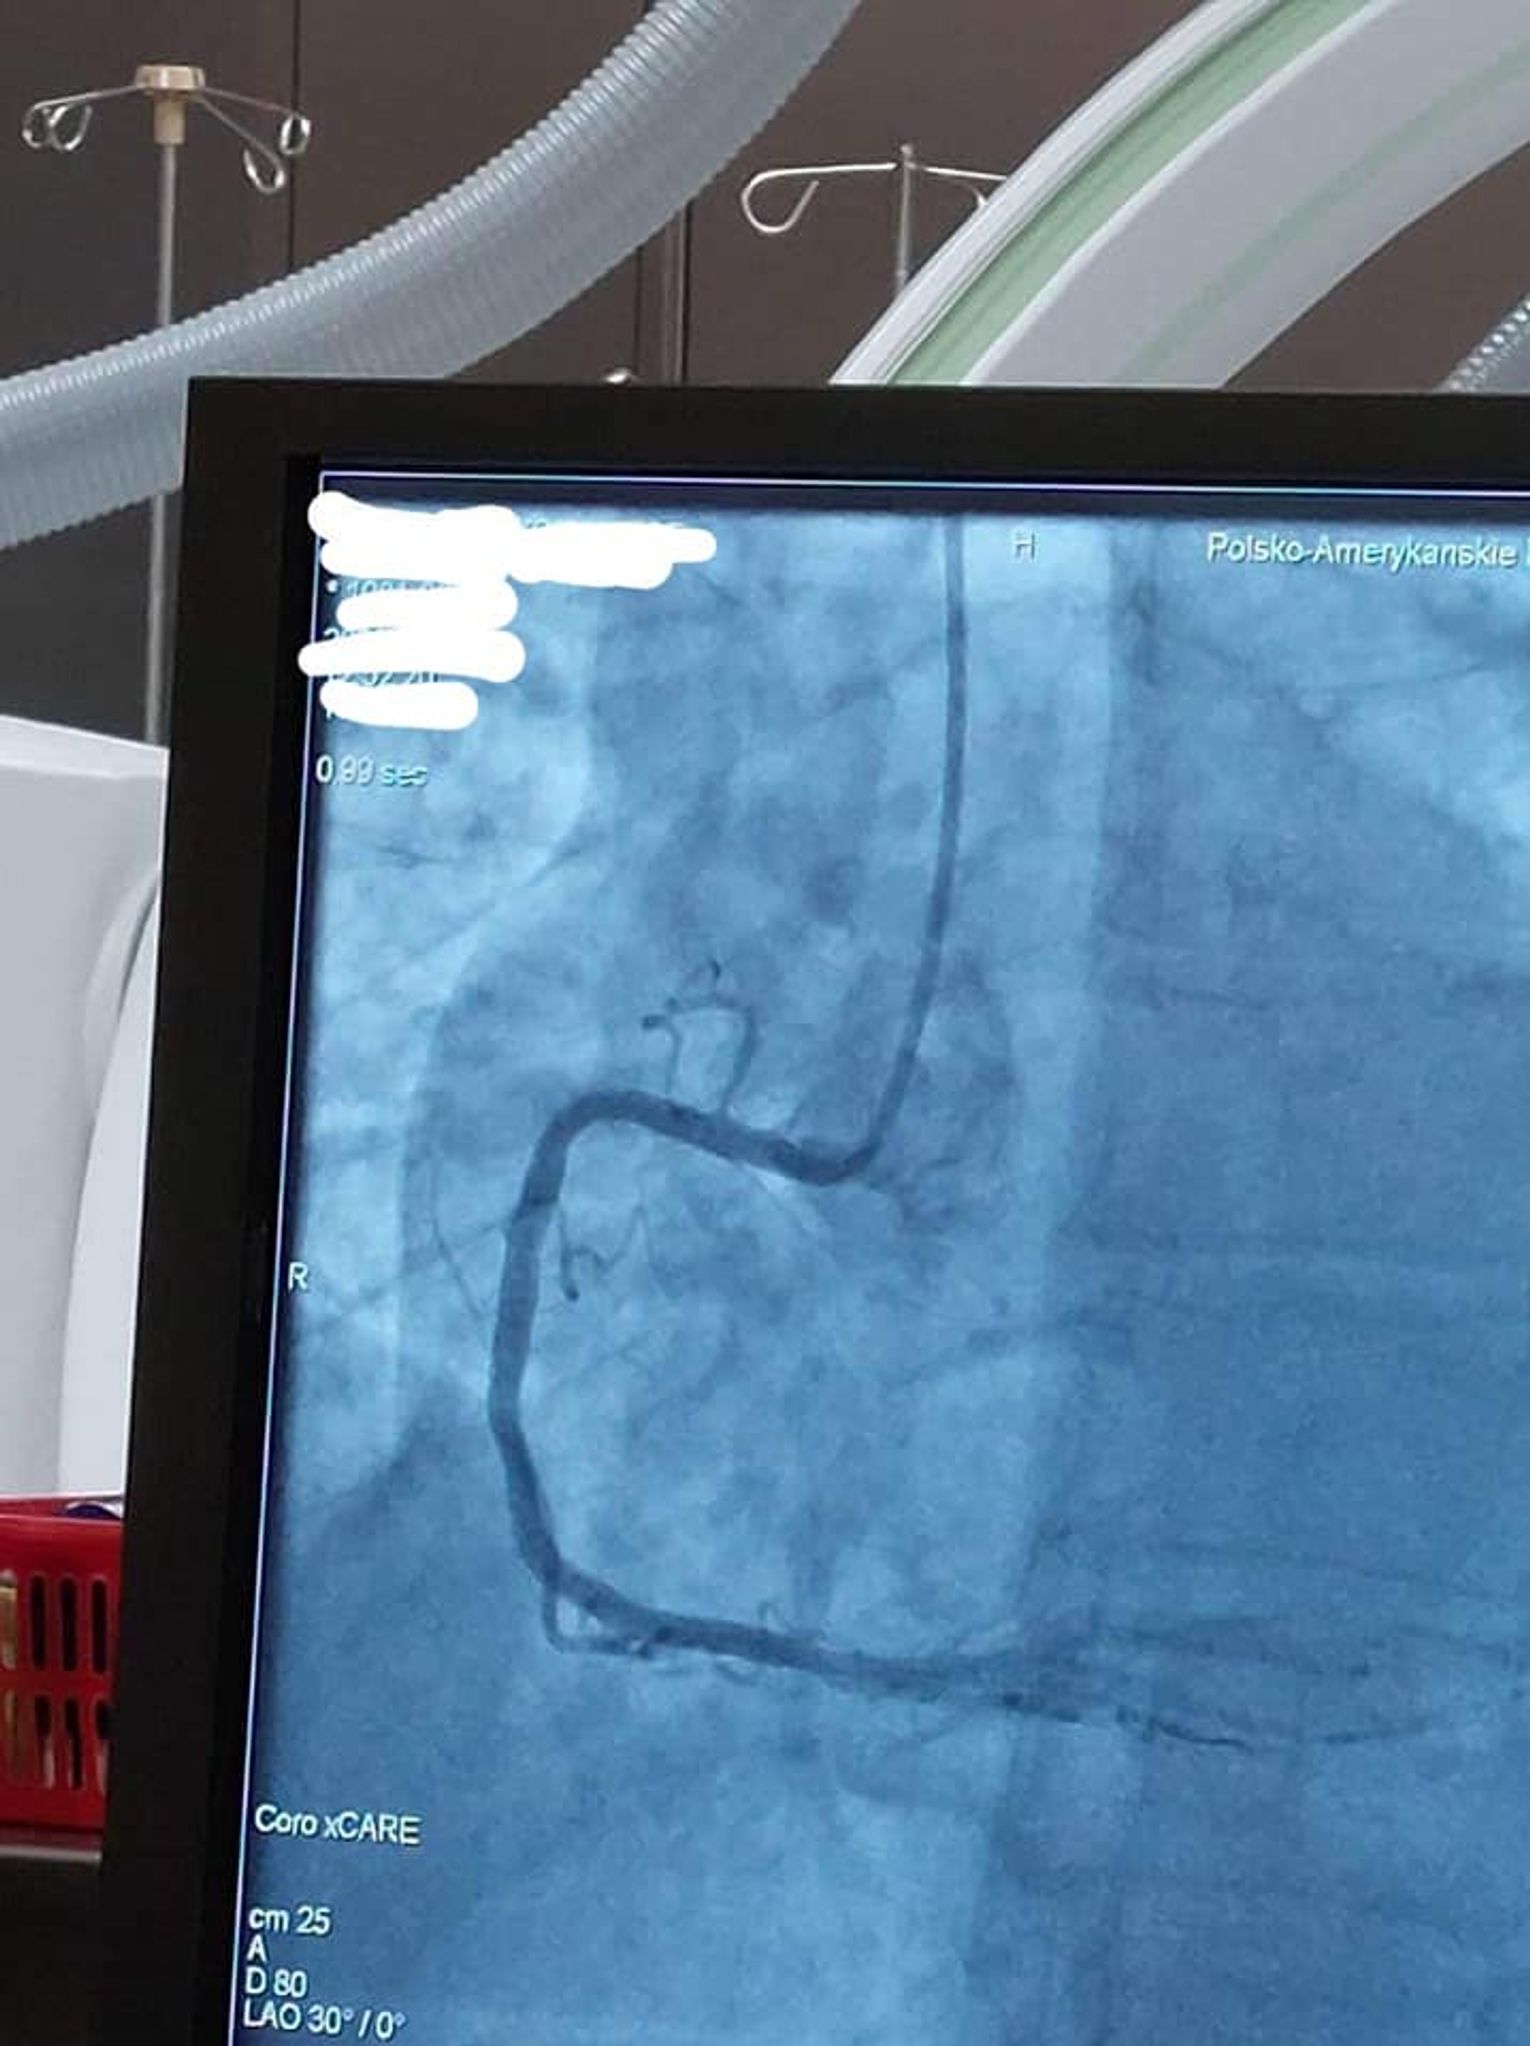

W wizycie udział wzięli: Julia Szukalska, Magda Grela i Kuba Różański oraz dyrektor szkoły Katarzyna Arciszewska-Stępień. Wyjazd był nagrodą w konkursie "Serce na dłoni" organizowanym na początku marca. Po przyjeździe uczniowie przebrali się w medyczną odzież i rozpoczęli obchód po oddziale kardiologii inwazyjnej z ordynatorem dr Januszem Prokopczukiem. Rozmawiając z personelem dowiedzieli się, jak wygląda dzień w klinice. Uczniowie mogli zobaczyć, jak przebiega zabieg wszczepienia rozrusznika serca, koronarografia, elektrokardiografia, wkłucie dożylne i przezprzełykowe echo serca. Nie zabrakło pytań dotyczących studiów na kierunku lekarskim i specyfiki pracy w tym zawodzie. Spotkanie było niesamowicie ciekawe, sprawiło uczniom wiele radości i dodało im motywacji do nauki, by spełnić swoje marzenia o studiach medycznych.

28 marca trójka uczniów II LO im. Mikołaja Kopernika w Kędzierzynie-Koźlu odwiedziła Polsko - Amerykańską Klinikę Serca w Koźlu.